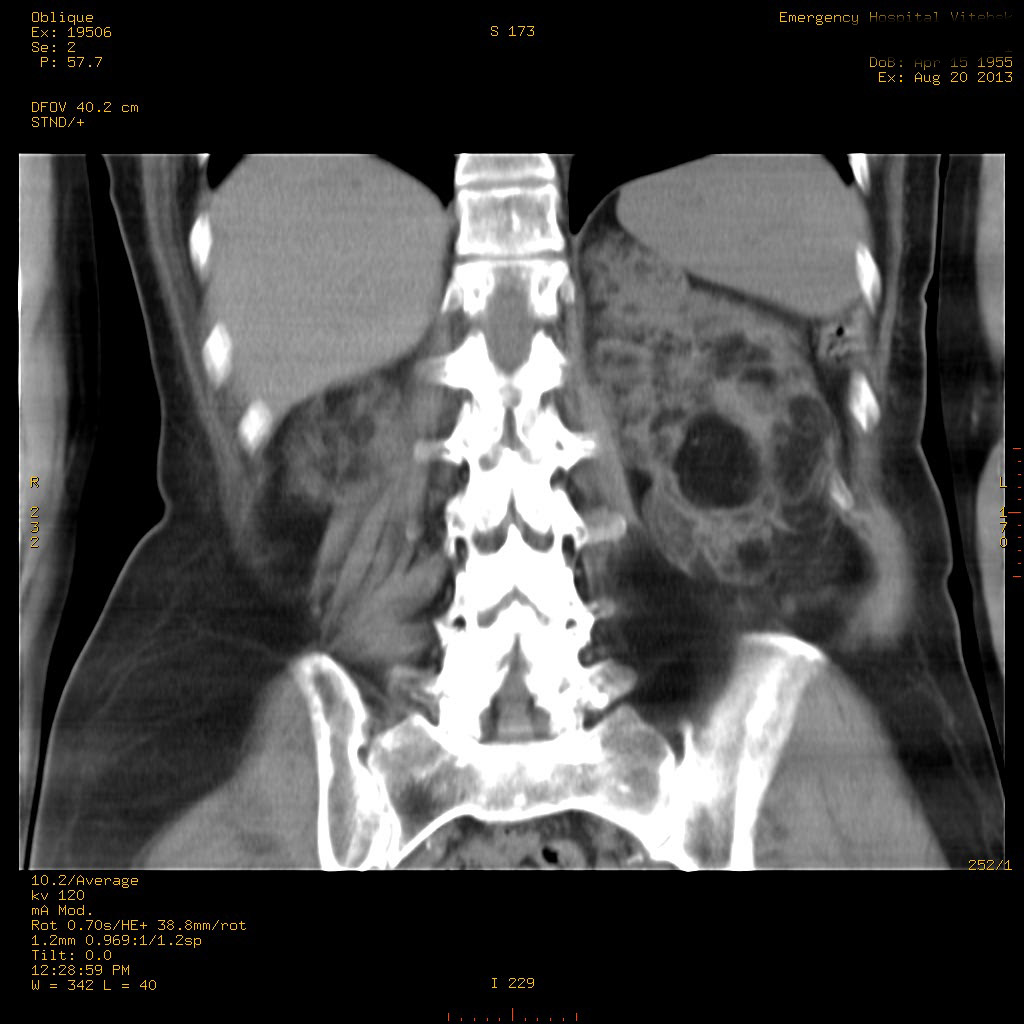

УЗИ почек - туберозный склероз

Пожилая женщина с нормальными мочевиной и креатинином.

Ангиомиолипоматоз почек , думаю компонент туберозного склероза.

Да, туберозный склероз.

Случай консультирован на кафедре радиологии Католического университета г.Лёвен (Бельгия) - зав каф. профессор Р.Оуен.